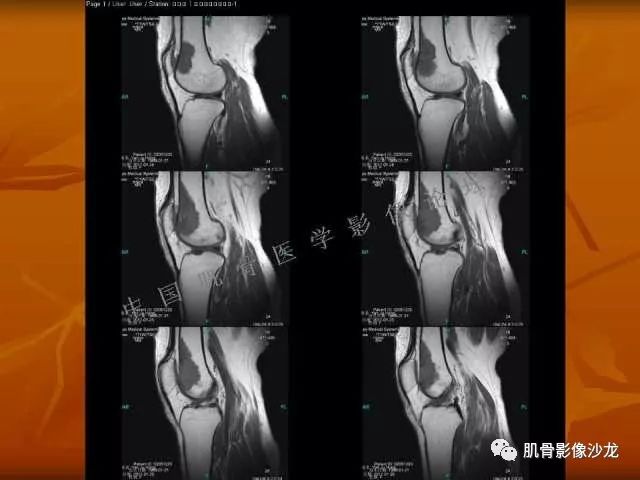

雪舞 :第二例,位于骶骨,有骨质破坏并有软组织肿块,软组织肿块边界清

雪舞: 第二例我们能够看到破坏与软组织肿块不成比例,软组织肿块大,破坏小

雪舞 :第二例挺难的,骨质破坏是溶骨性的,局部皮质中断,软组织肿块外缘光滑

1、软骨肉瘤可以有膨胀性骨质破坏(病例3,4),可以有溶骨性骨质破坏(病例2),局部皮质因为破坏变薄,中断 ;

2、软骨基质T2WI高信号,软骨小叶分叶状,也就会出现高老师提到的骨内膜扇贝形压迹。一般认为骨内膜扇贝形压迹超过骨皮质厚度的2/3是软骨肉瘤在长管状骨的特征性表现。如上图。3、软组织肿块或肿胀;